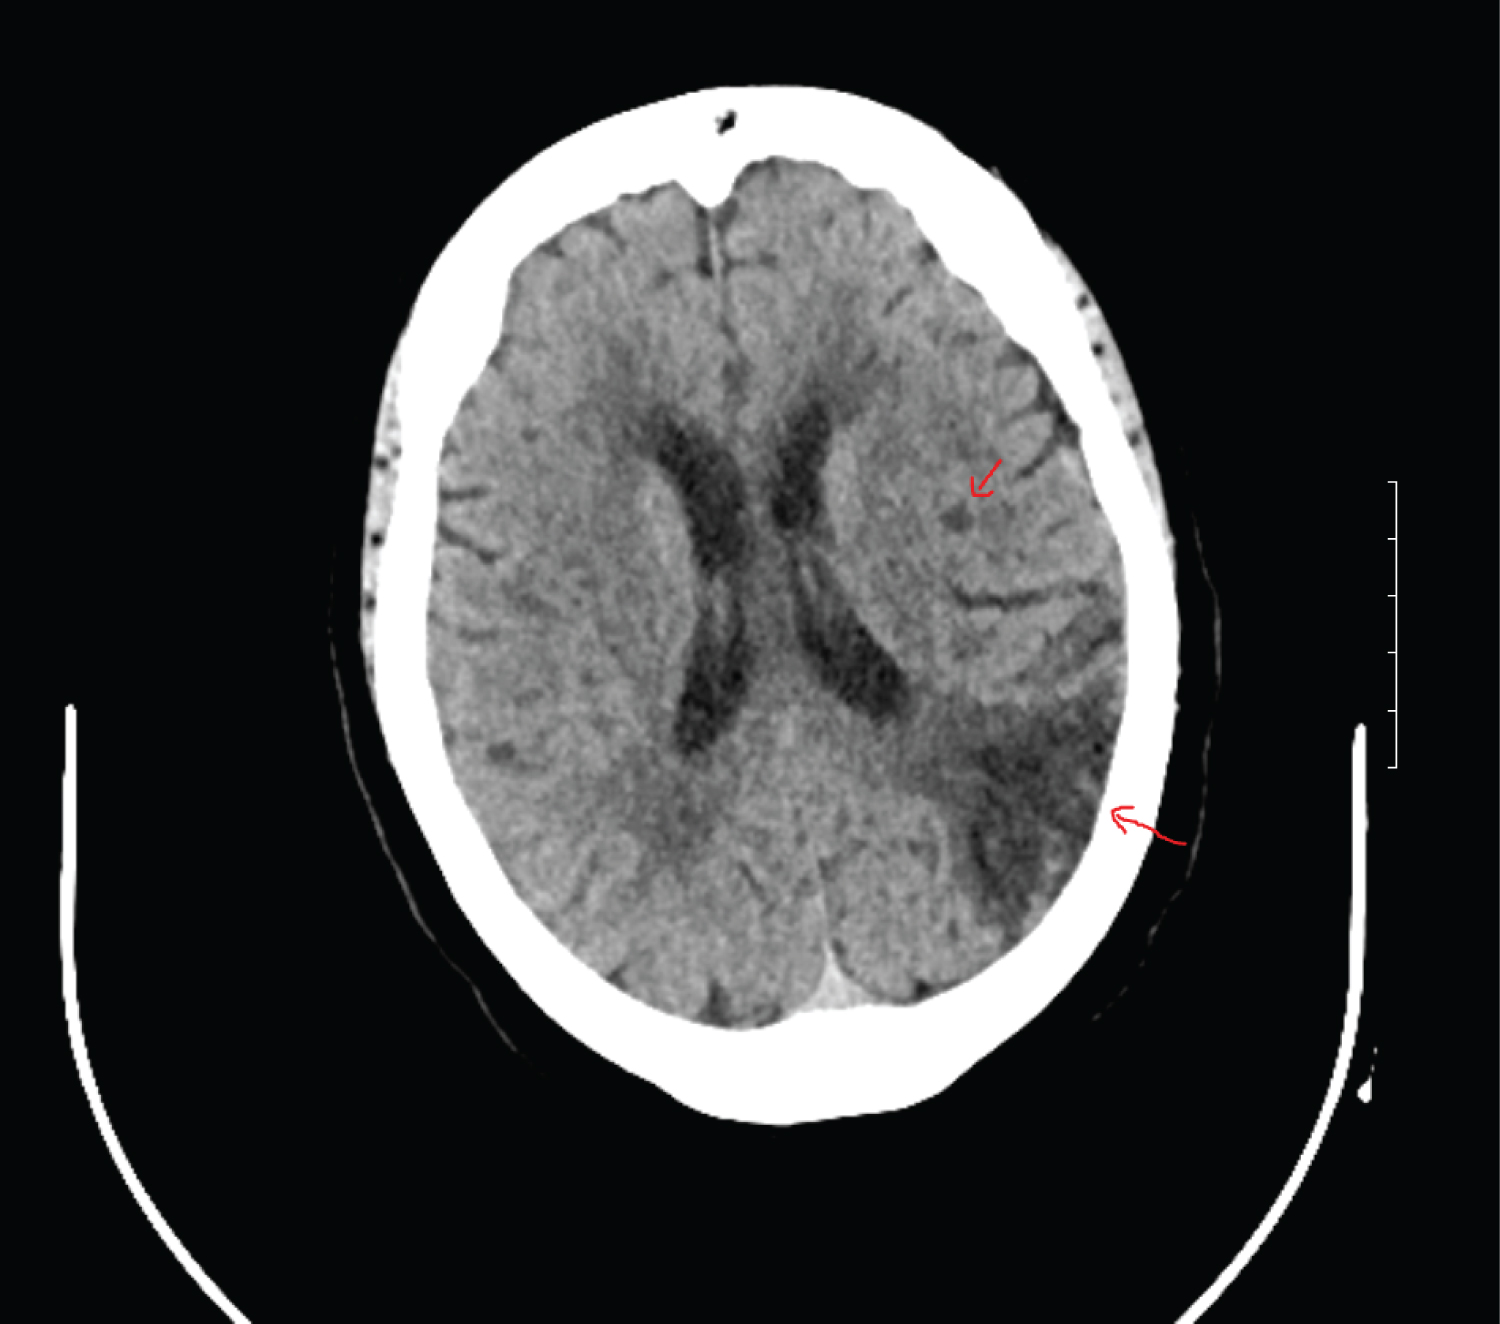

ZD's daughter reported the patient's condition did not improve and she was taken back to the emergency room 5 days later with sudden onset aphasia, right facial droop, and right sided weakness. She was emergently evaluated by neurology, and she was started on a tissue plasminogen activator (tPa) infusion, and admitted to the intensive care unit (ICU). Per hospital protocol, two troponin levels were drawn and both results came back normal. An echocardiogram was completed and showed no significant valvular heart disease and normal left ventricular systolic function. An electrocardiogram (EKG) was not available from this hospitalization. The patient developed a fever, elevated D-dimer (24+), and leukocytosis was noted (white blood cells were 15+). The following labs were drawn to assess renal function: Creatinine: 0.76 mg/dL and Blood Urea Nitrogen: 8 mg/dL. The following labs were not obtained during this hospital stay: IL-6 level, fibrinogen, lymphocyte and neutrophil count, ferritin, or cardiac function. A fourth COVID-19 RT-PCR test was completed as well as blood and urine cultures. The urine culture was negative for Legionella antigen. Ceftriaxone and vancomycin were started empirically. The fourth COVID-19 RT-PCR test came back positive. Magnetic resonance imaging (MRI) and magnetic resonance angiography (MRA) of the head and carotid arteries were completed and showed the patient had a large chronic appearing infarct involving the left temporal parietal cortex. Figure 2 presents the imaging of the patient's completed MRI. A chest X-ray was also completed and showed minimal sub segmental bibasilar atelectas is with improvement in the previously visualized patchy opacities. ZD was placed on enoxaparin 40 mg subcutaneously every 12 hours for anticoagulation therapy. Her antibiotics were changed to ceftriaxone and azithromycin, then Zosyn for broader coverage. Her white blood cells started trending downwards and she became afebrile. She was transferred to the medical floor and her symptoms continued to improve. ZD was evaluated by Speech Therapy and advanced to a regular diet. The antibiotic was changed again to Levaquin 500 mg for 3 days and then discontinued.

Figure 2: This MRI of the brain shows evidence of hypo-attenuation in the left posterior centrum ovale without any associated ex vacuo dilation of the left lateral ventricle which is indicative of a recent infarct. View Figure 2